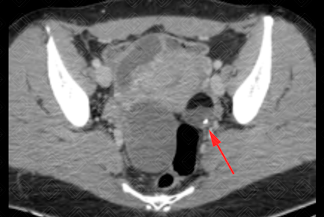

Texto alternativo para a imagem Figuras 1, 2 e 3. Créditos: Dra. Elazir Mota - Rio de Janeiro/RJ.

Descrição das figuras 1, 2 e 3: Tomografia computadorizada do abdome. Estudo pré e pós-contraste (fase portal). Observa-se lesão heterogênea, bem definida, com nível líquido-gorduroso e foco de calcificação ("sinal da pokebola"). A gordura é identificada por uma densidade abaixo negativa (seta vermelha). Essas características de imagem permitem que o diagnóstico de teratoma ovariano maduro possa ser sugerido.

• Tomografia computadorizada do abdome e pelve: O estudo será realizado com contraste venoso idealmente, para melhor caracterização da lesão. A TC, no caso específico do teratoma maduro, possui uma sensibilidade alta para sua caracterização (cerca de 98%). Nela encontram-se áreas com densidade negativa (conteúdo gorduroso), calcificações e, na maioria dos casos, o nódulo mural (Rokitansky) no interior da formação cística. Nesses casos, é possível sugerir o diagnóstico (como nas imagens acima);